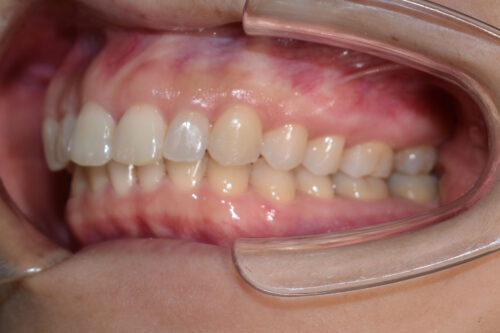

ワイヤー矯正治療10か月後です。

ワイヤー期間 10か月, 13回来院

かみ合わせをあげながら

歯の並びをそろえていくことで

歯をぬかなくても

出っ歯にならずに

非抜歯矯正治療で

咬合させることができます。